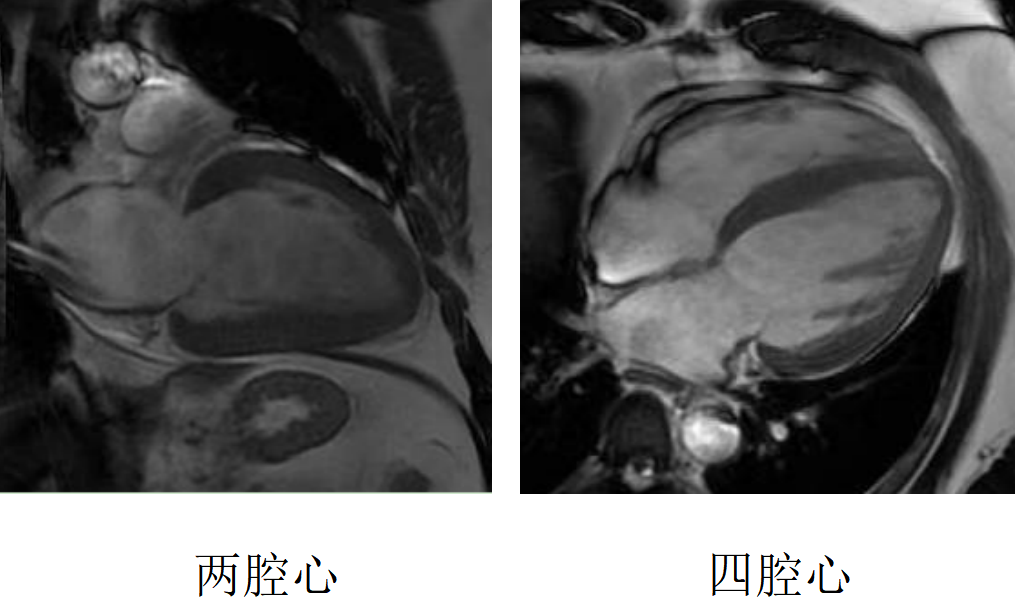

心臟磁共振被稱為心臟“一站式”檢查,通過多參數(shù)成像能夠?qū)π呐K的結(jié)構(gòu)、功能、室壁運動、心臟瓣膜、心肌灌注和活性進行“一站式”評估。主要通過電影序列(短軸、兩腔心、四腔心、三腔心)、T2WI序列、首過灌注序列以及延遲強化序列對心臟進行綜合成像。

擴張型心肌病

肥厚型心肌病,舒張末期心尖形似“黑桃A征”